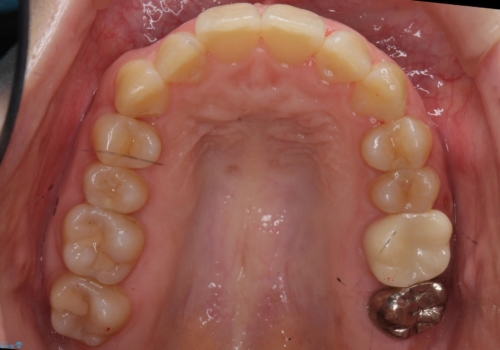

結果それなりに並んで問題ない状況にはなったと思います。

奥歯を後ろに送るために、矯正用ミニスクリューを使用しました。

また、下顎の前歯から奥歯にかけて歯を少し削るIPRを行なっています。